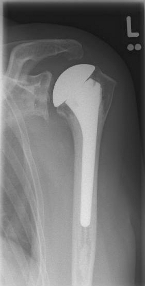

left: X-ray image of an omarthrosis

Conventional stem prostheses for omarthrosis and acetabular wear

right: anatomical shoulder prosthesis with glenoid replacement (Affinis type, Mathys company)

Short stem prostheses as modern implants for omarthrosis and acetabular wear

left: X-ray image of a short-shaft prosthesis

right: Short-shaft prosthesis (Affinis Short type, Mathys company)